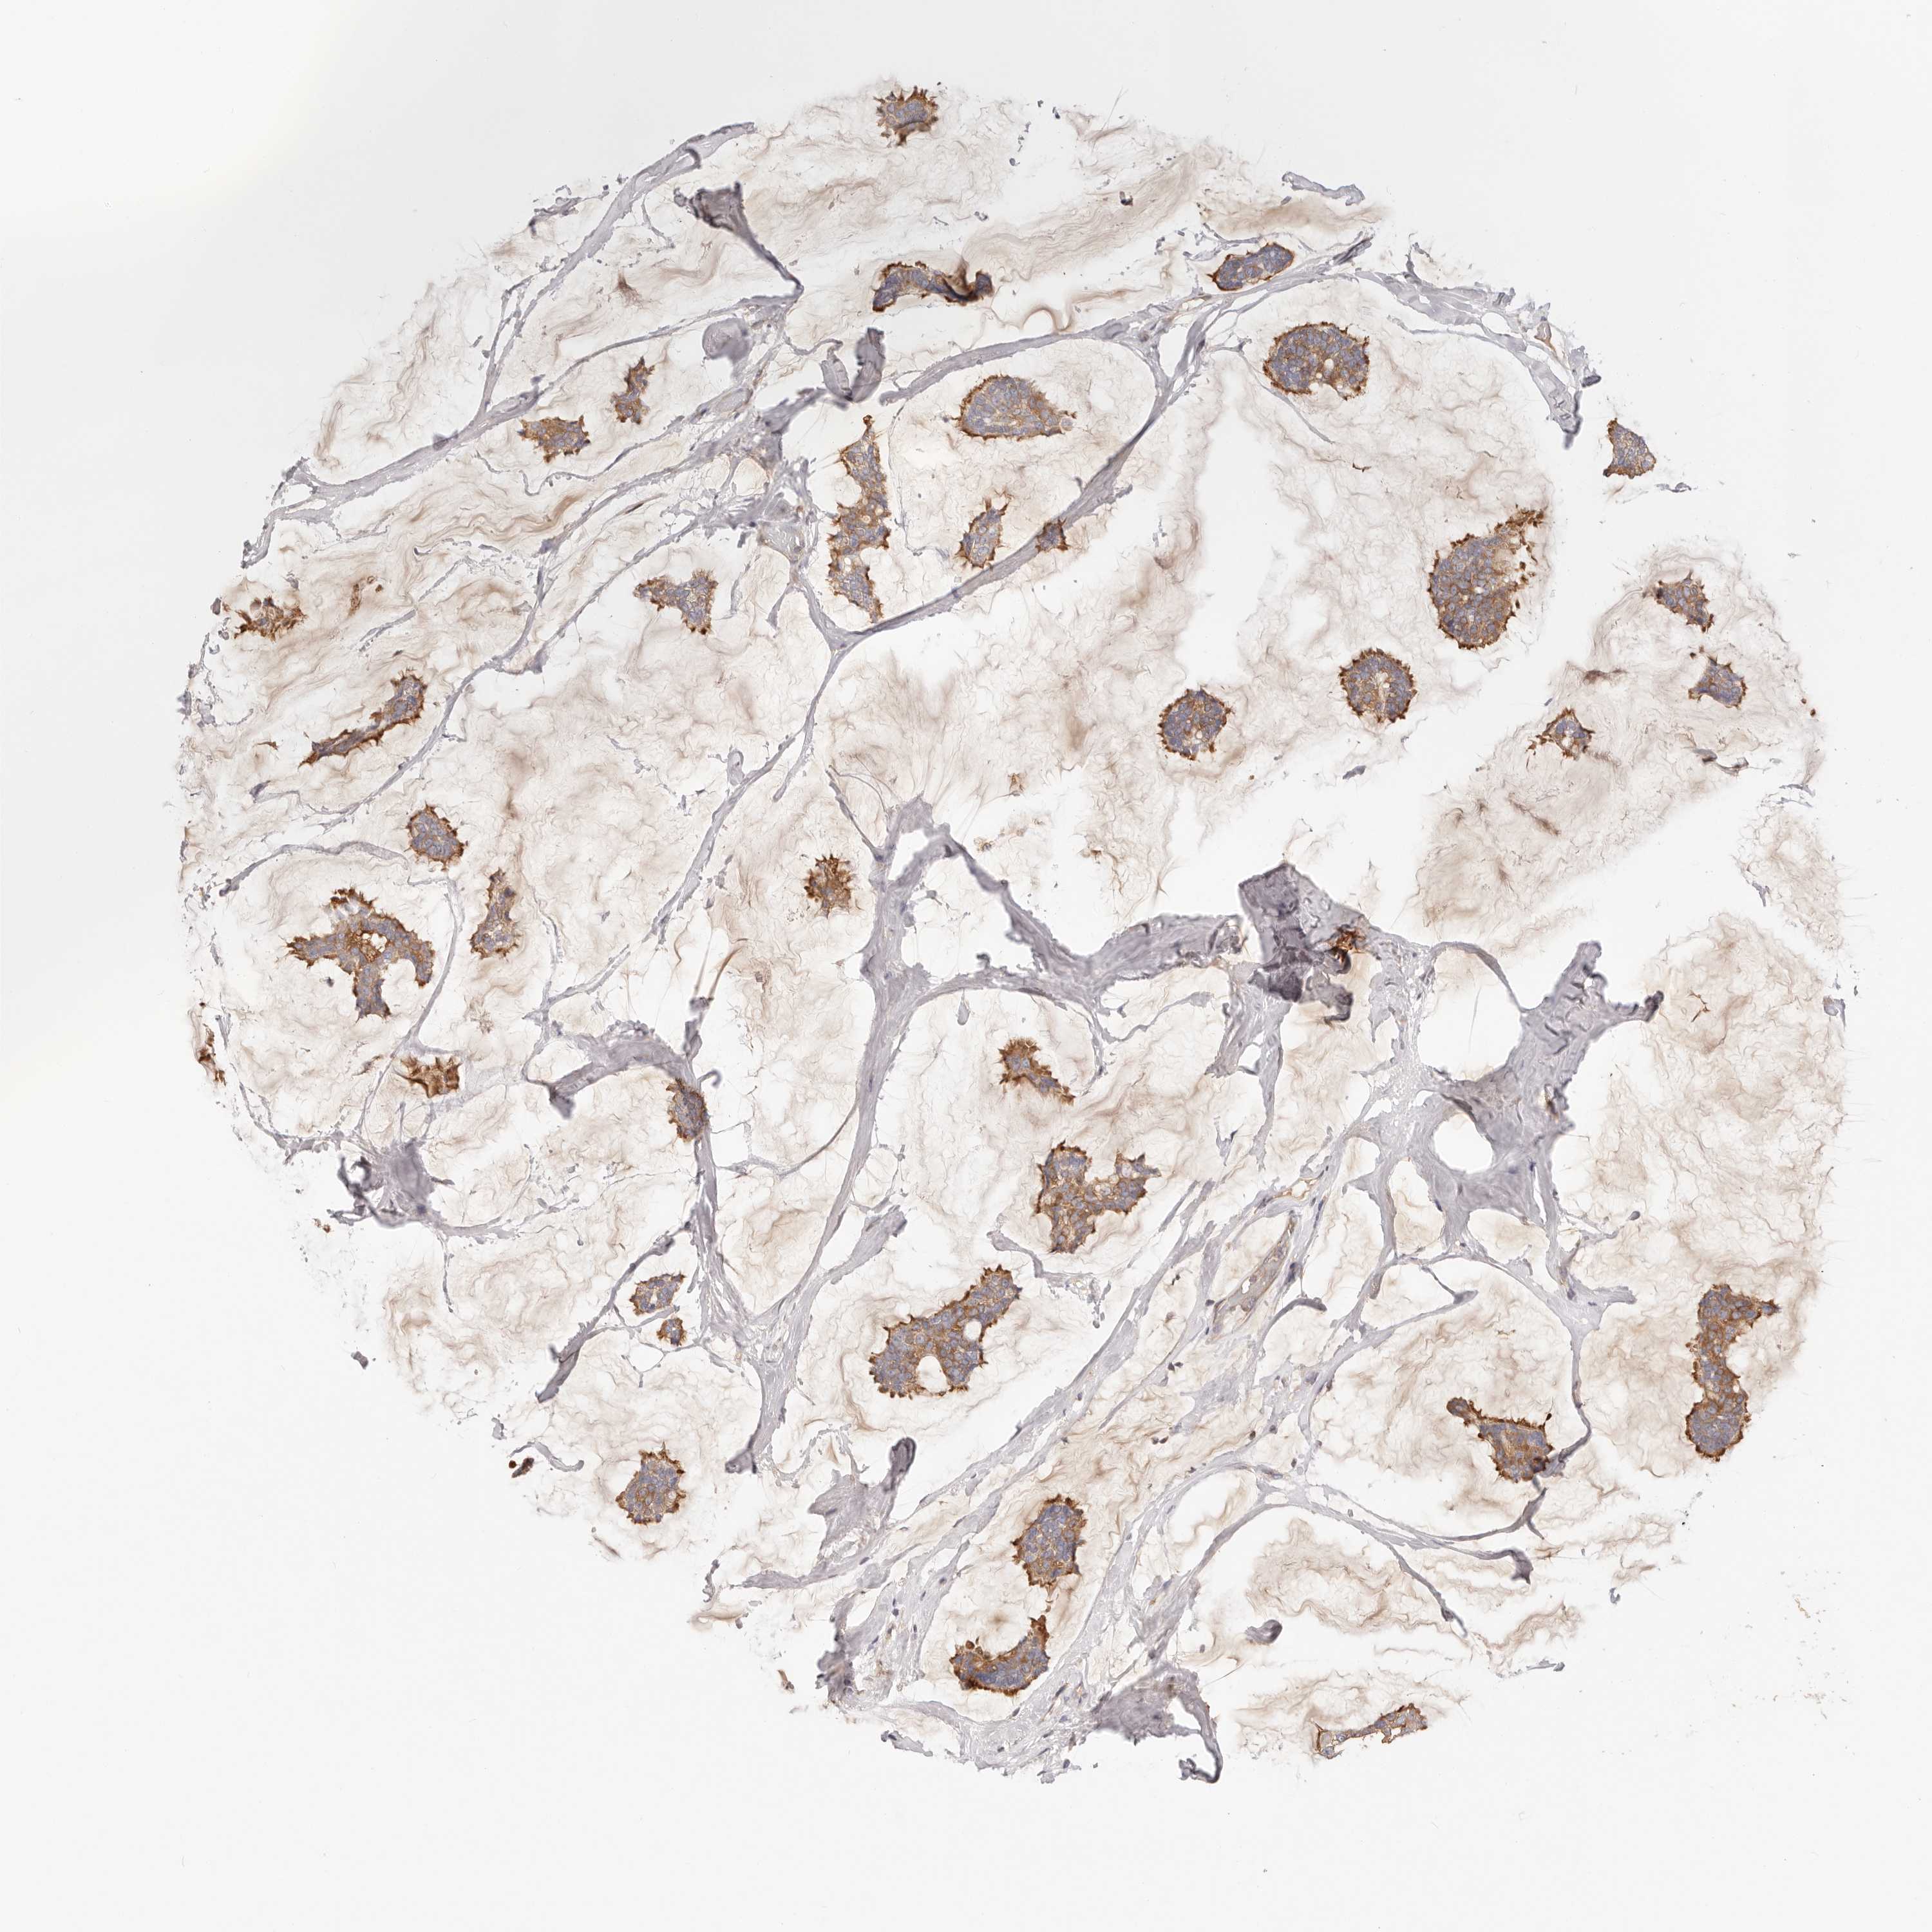

CANCER BREAST CANCER Show tissue menu

BRCA TCGA BRCA VALIDATION PROTEIN EXPRESSION